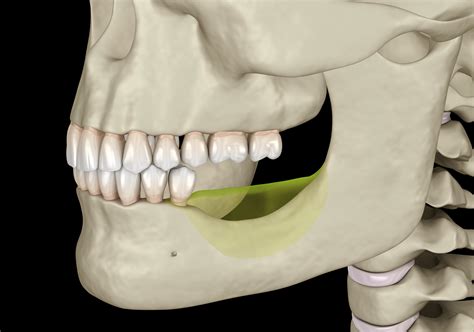

The jaw, or mandible, is the largest and strongest bone in the face. It plays a crucial role in functions such as chewing, speaking, and facial expressions. The jaw is connected to the skull by the temporomandibular joints (TMJ), which allow for the movement of the jaw. A jaw bone broken can disrupt these functions and cause significant discomfort and pain.

Jaw Bone Anatomy